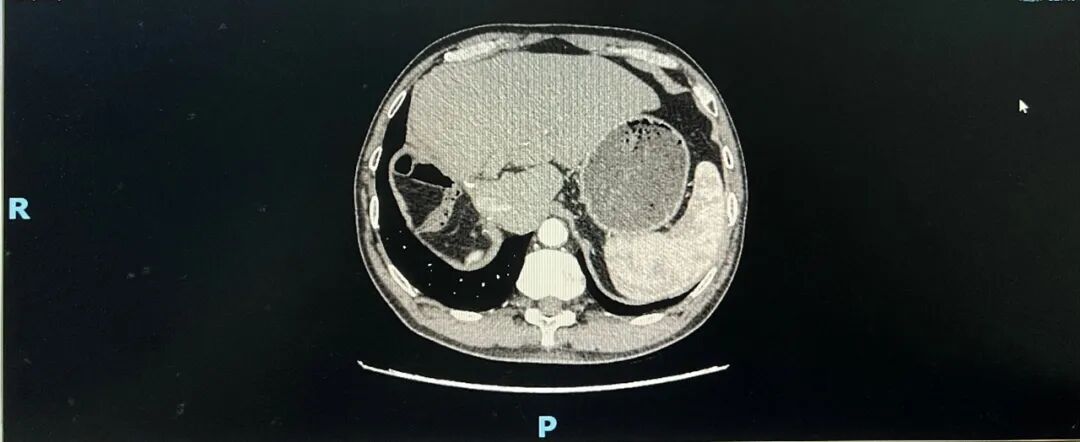

➣ 2020-11-3,CT检查示:残肝增大,肝断面有少许的渗出,肝内未见新生病灶,门静脉未见充盈缺损。

➣ 2021-04-8,CT:肝右叶、胆囊未见显示,考虑术后改变,术区未见确切肿瘤复发征象。

➣ 2021-11-23,CT:肝右叶、胆囊未见显示,考虑术后改变,术区未见确切肿瘤复发征象。

➣ 2023-02-9,CT:术区未见确切肿瘤复发征象。

➣ 2024-10-14,CT显示术区未见确切肿瘤复发征象。